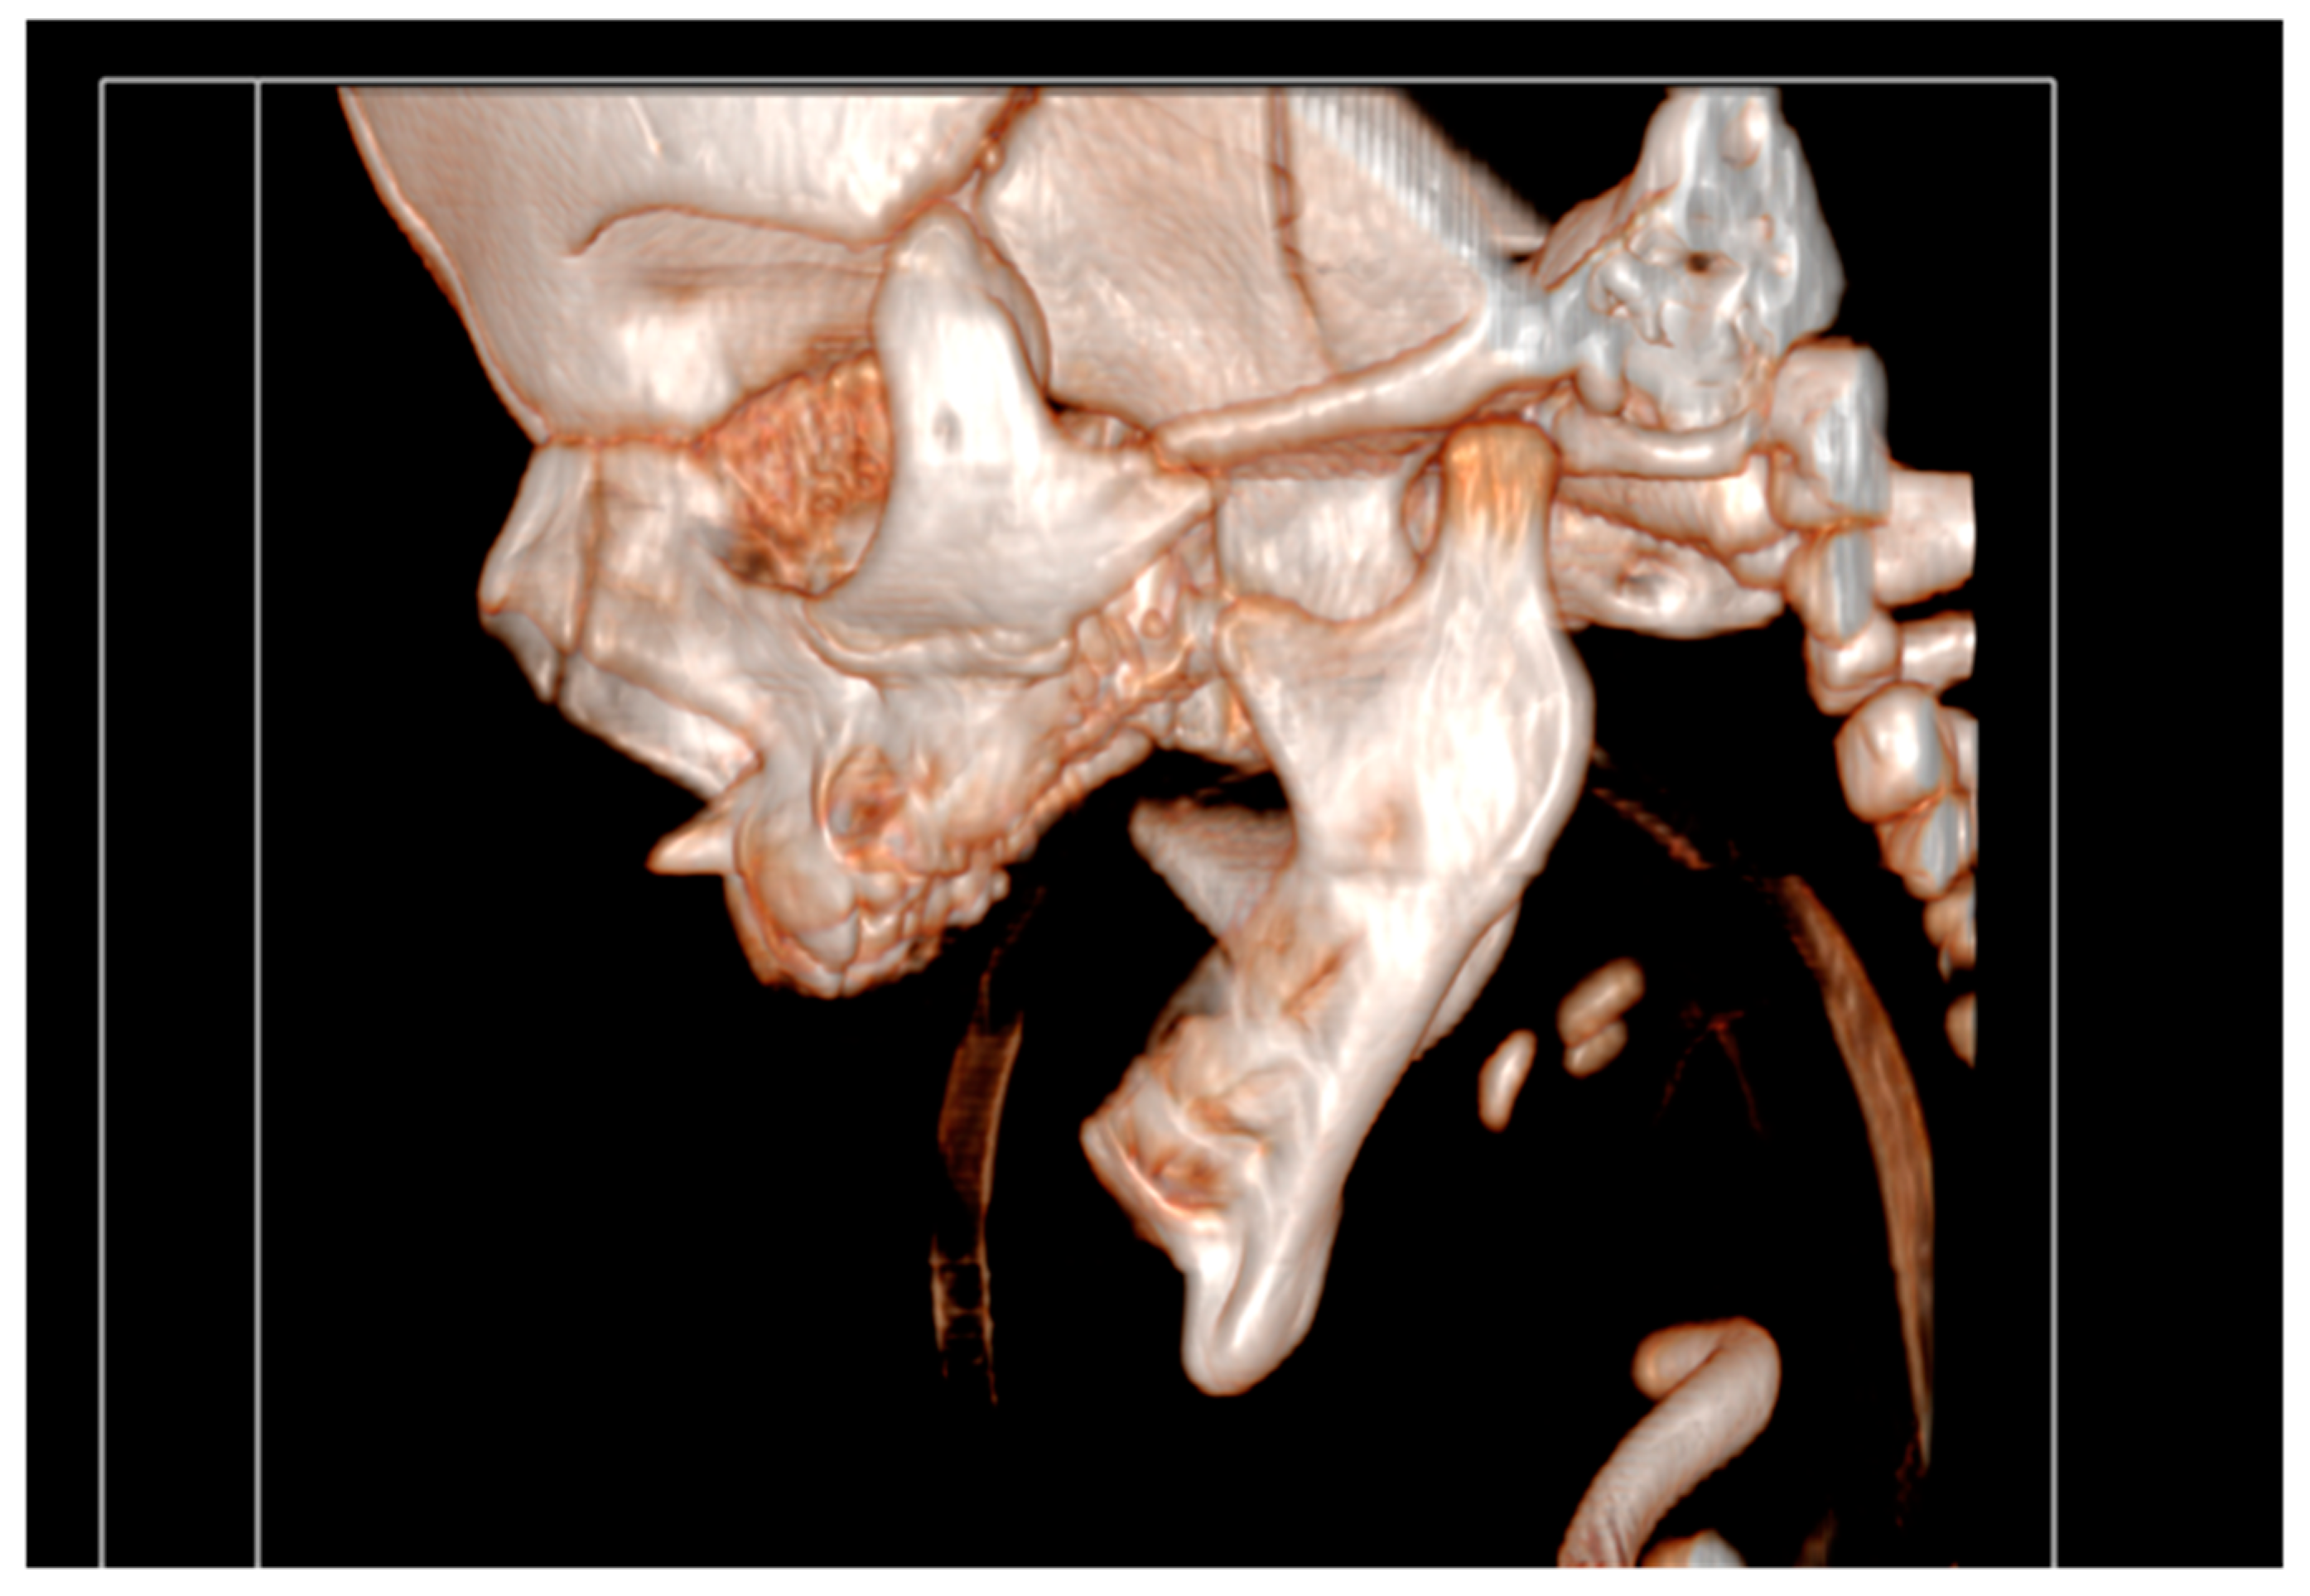

Cranial ultrasound showed no pathological findings, except for discretely hyperechoic periventricular white matter. A computed tomography of facial region described mandibula as hypoplastic and narrow (Figure 3).

It had underdeveloped body region and pointed chin. Only three tooth germ of the lower frontal teeth was present, that was only one lower medial incisor and two lateral incisors. Temporomandibular joints were normal (Figure 4).

Figure 3. A computed tomography of a narrow and hypoplastic mandibula.